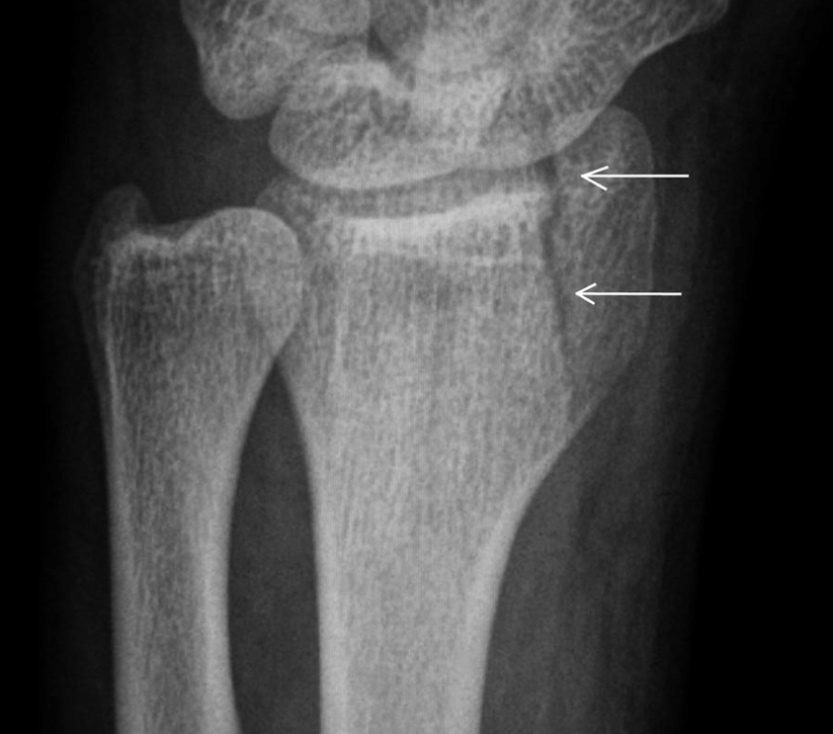

Que es ?

A

FX CHAUFFER